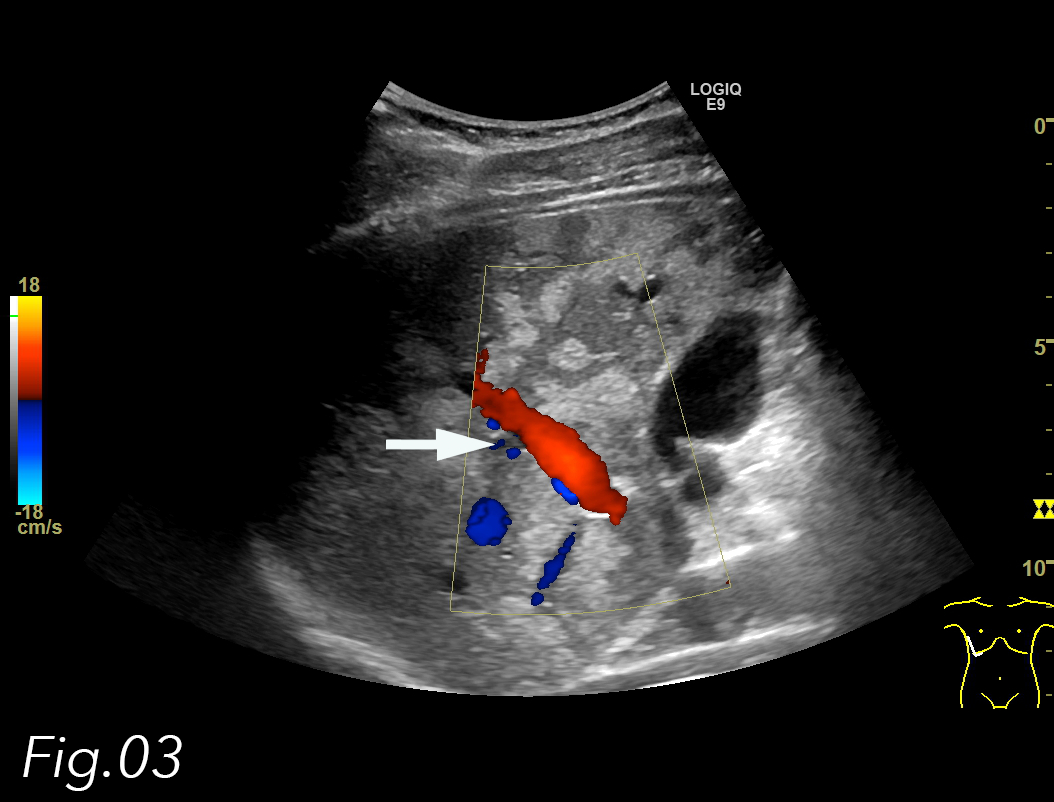

The portal vein and hepatic artery had normal Doppler signals and there was no invasion of the vessels (Fig. 3). Normally, a contrast-enhanced ultrasound (CEUS) would have been performed, but due to the large size, the irregular borders and the patient’s comorbidities, an MRI of the abdomen with liver specific contrast agent (Primovist) was performed to characterize it further. In- and out-of-phase images showed that the lesion was focal fatty infiltration, but with an unusual large size (Fig. 4, 5, 6). The behavior of the lesion after contrast administration was similar to the surrounding liver parenchyma.

Fig. 3: US image of the liver. Semi sagittal plane through the right liver lobe with color Doppler in the right portal vein showing focal fatty infiltration in segment V and VIII – note no distortion of vessels (arrow).